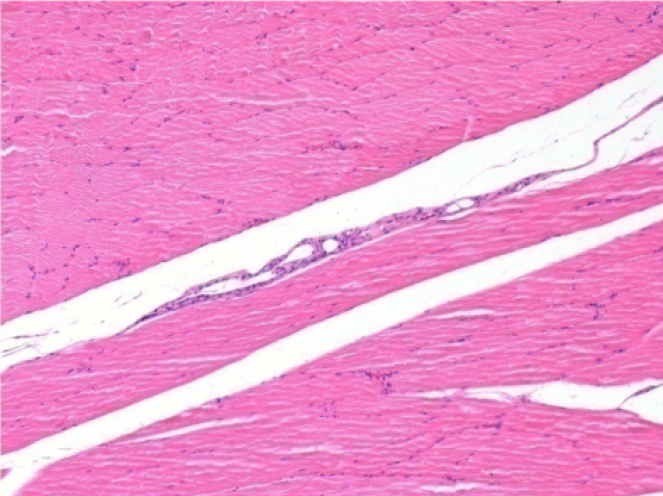

Control

Comentario: Nada que declarar después de la inyección de solución salina.

L: Pretibial-Sin tratamiento

R: Pretibial-Después de 0,1 ml de NaCl 0,9% IM